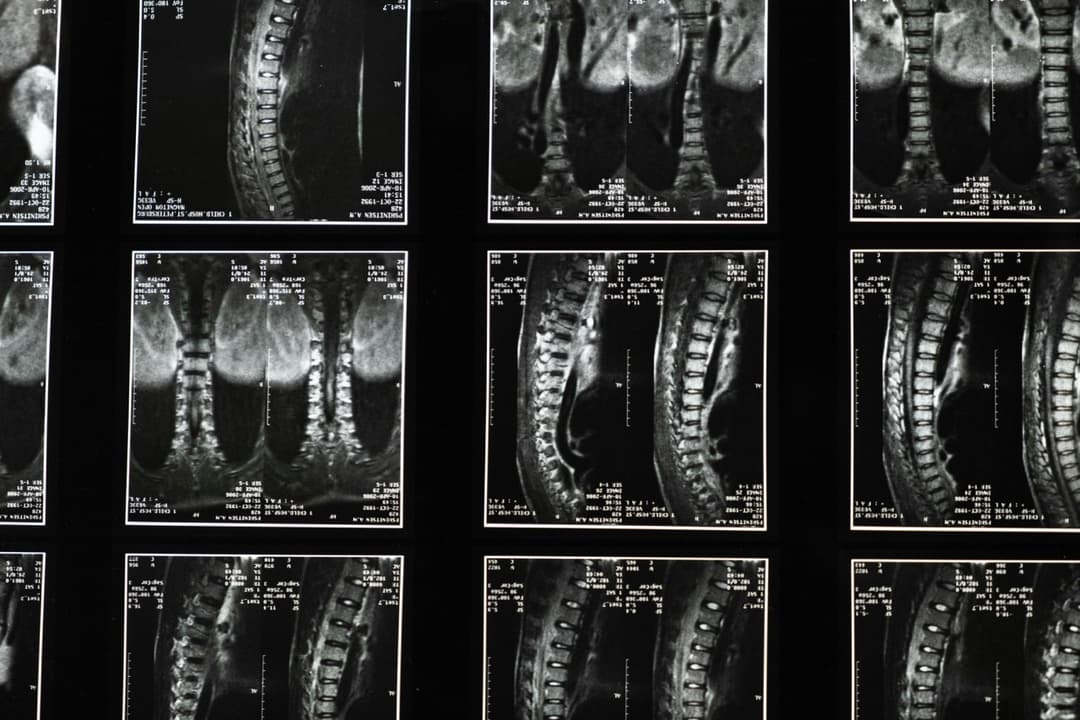

Le docteur en chiropratique est le spécialiste du système neuro-musculo-squelettique, c'est à dire qu'il peut diagnostiquer et traiter les conditions en lien avec les nerfs, les muscles et les os.

Essentiellement, la chiropratique considère que notre santé dépend du bon fonctionnement de la colonne vertébrale et du système nerveux, ainsi que de l'équilibre musculaire. Le but poursuivi par le chiropraticien n'est pas de simplement diminuer la douleur ressentie au dos ou ailleurs.

Il s'assure plutôt que le système nerveux, qui ressemble à «une autoroute de communication» soit capable de transmettre efficacement l'information entre le cerveau et le corps dans les 2 sens. De cette manière, tous les systèmes du corps peuvent fonctionner à leur plein potentiel.